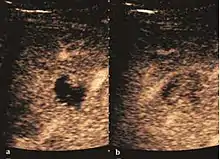

The ultrasound appearance is a well defined lesion, with very thin, almost unapparent walls, without circulatory signal at Doppler or CEUS investigation. The content is transonic suggesting fluid composition. The presence of membranes, abundant sediment or cysts inside is suggestive for parasitic, hydatid nature. Posterior from the lesion the acoustic enhancement phenomenon is seen, which strengthens the suspicion of fluid mass. They typically displace normal liver vessels but no vascular or biliary invasion occurs.

Hydatid liver cyst. Diagnostic criteria are the presence of membranes and sediment inside.